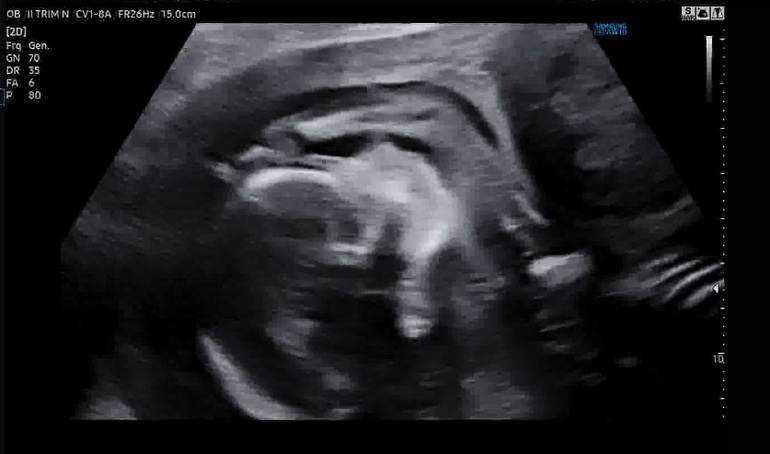

Фото с узи

Ножка футболиста и мячик)